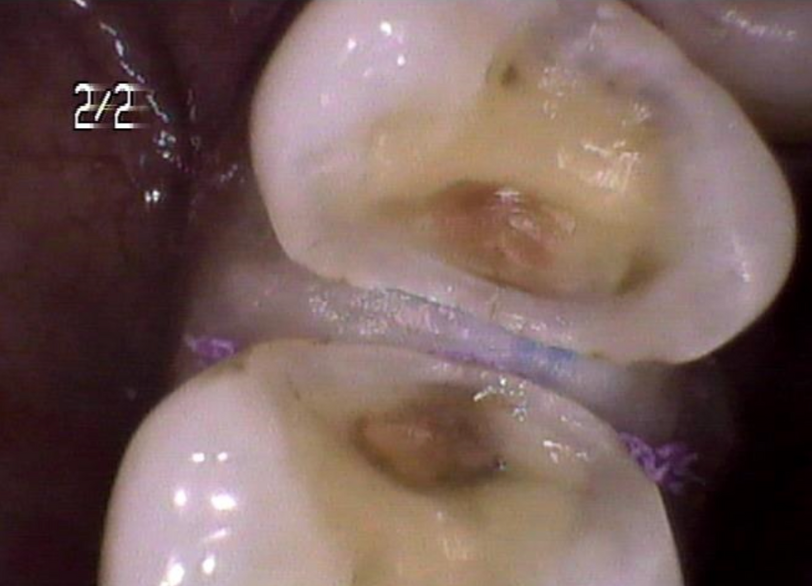

術中銀歯を除いた状態

う蝕を除き切った状態